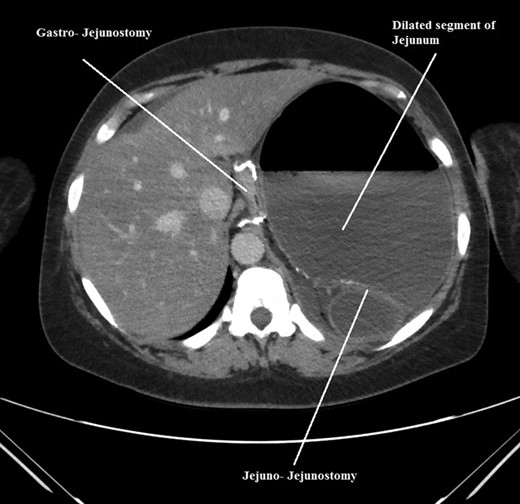

CT scan of her abdomen and pelvis revealed findings of previous gastric bypass with gastric pouch severely dilated and air-fluid levels measuring up to 17 cm. The excluded portion of the stomach was noted to be decompressed as a result of dilated gastric pouch. The proximal to mid small bowel was fluid-filled and severely dilated to approximately 4 cm. Distal small bowel and colon were decompressed. There was no evidence of pneumoperitoneum. Based on these findings initial diagnosis was presumed to be gastric outlet obstruction with dilated gastric pouch. Fluid hydration and nasogastric tube decompression was continued. Patient was prepared to be taken to the operation room for emergent diagnostic laparoscopy.

The intraoperative findings were not consistent with the radiological findings (Figs 1–4). As shown in the CT scan of abdomen and pelvis; multiple loops of dilated small bowel were seen, more predominantly dilated and matted bowel complex just above the spleen. The dilated bowel complex was decompressed using needle aspiration to help reduction of the bowel loops. The ileo cecal junction was then identified and traced back to the perisplenic hilar region. The trifurcation of three bowel loops (Roux limb, biliopancreatic limb and common limb) were identified with identification of ligament of Treitz. The prior gastric bypass was of ante colic- ante gastric type and Peterson’s defect was not closed. The above described bowel trifurcation had sunken postero- inferior to the spleen and had herniated through a potential space underneath the spleen and torsed around the splenic vessels and hilum. This picture was consistent with perisplenic small bowel volvulus. As noted earlier there was a massively dilated proximal small bowel segment above the spleen, displacing it caudally. Careful adhesiolysis was performed inferior to the spleen to release the segment of the trifurcation. The bowel segments once reduced were assessed and appeared viable. Of note, the spleen appeared better perfused after reduction. The remnant hernia defect of size 2 × 3 × 2.5 cm around the hilar region was then approximated using interrupted non-absorbable sutures. Enterotomy at the decompression site was closed with non absorbable suture. All potential sites of IH were re-examined and there was no evidence of any other internal herniation. Coelomic cavity was thoroughly irrigated and operation concluded successfully. Postoperative hospital stay was uneventful, and the patient was discharged home after two days.

Axial CT scan of abdomen and pelvis showing, gastro-jejunostomy, Jejuno-Jejunostomy and dilated proximal small bowel segment.